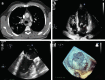

Mitral valve and right ventricular thrombi possibly caused by heparin-induced thrombocytopenia